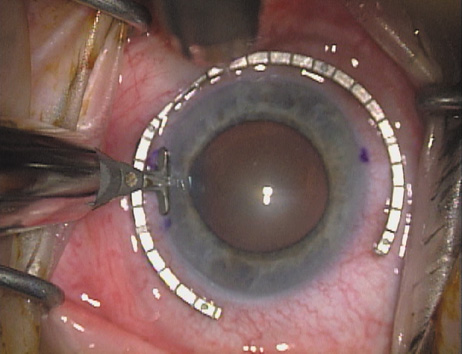

Case 2 is a 79-year-old woman who presented with a very dense left cataract. Her refraction was recorded at −2.25 +2.75 × 125 with a difficult end point. Her manual keratometry and topography measurements were consistent and revealed slightly less than 1.75 D at 120 degrees. Because of the questionable refraction, greater value was placed on the corneal measurements. Based upon the cataract nomogram, the plan was for paired LRIs of 40 degrees to be placed over the steep 120-degree axis (Figs. 1219).

Fig. 15. Total arc length equals 40 degrees. (Reprinted from Hardten DR, Lindstrom RL, Davis EA. Phakic Intraocular Lenses: Principles and Practice. Thorofare, NJ: SLACK Incorporated, 2004, with permission.)